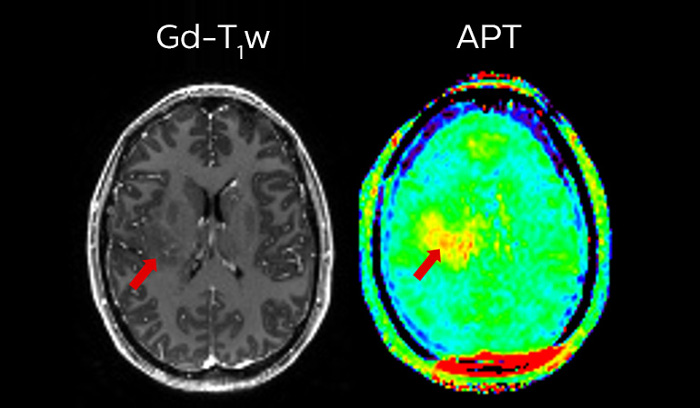

3 Compressed SENSE and APT are work in progress and not for sale in the USA

APT** and REACT**: The next steps towards non-invasive imaging strategies for pediatric MRI

Jeffrey H. Miller, MD

Vice Chair of Radiology for Research and Academic Affairs, Phoenix Children’s Hospital, Phoenix, AZ, USA